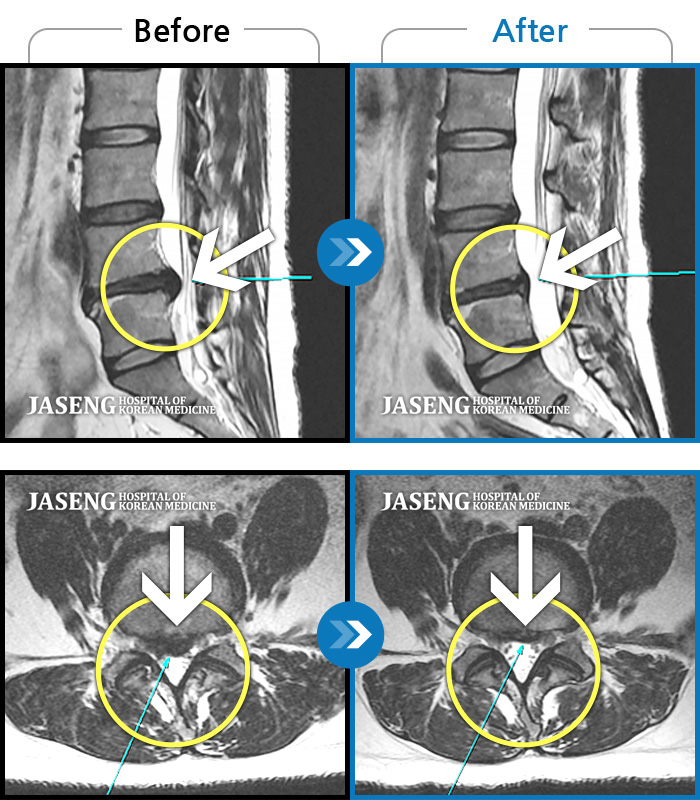

MRI 치료사례

요통, 우측 엉치 통증 및 양측 종아리 비증